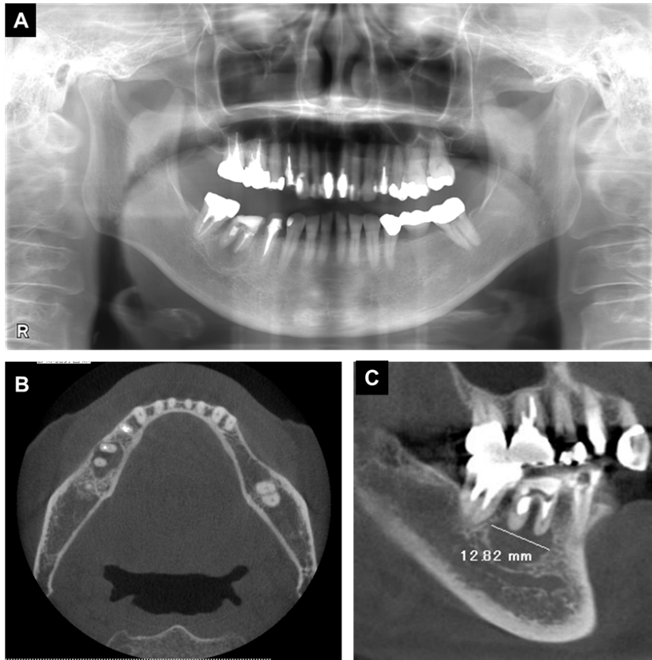

In an intraoral examination, temporary sealing with cement was observed on the right mandibular first molar (Figure 1A). Although intraoral examination showed no obvious gingival swelling around the roots of the right mandibular molar region, panoramic radiography showed a cystic lesion around the root apices of the right mandibular first molar (Figure 2A-C). Therefore, we selected tooth extraction and cystectomy as treatment. Although the patient’s preoperative platelet count was 36×103/μL, which was below the normal range, we performed tooth extraction and cystectomy under intravenous sedation without platelet transfusion based on the hematologist’s opinion that the patient was at low risk of hemorrhagic diathesis. No abnormal bleeding was observed in the socket, and the operative site was packed with Surgicel® (Ethicon Inc., New Brunswick, NJ, USA) and suture; a splint was then placed for hemostasis.

Figure 2. X-ray examination findings at the initial visit. (A) Panoramic radiography, (B, C) Computed tomography images. Radiolucent findings were observed at the root apex of the first molar.